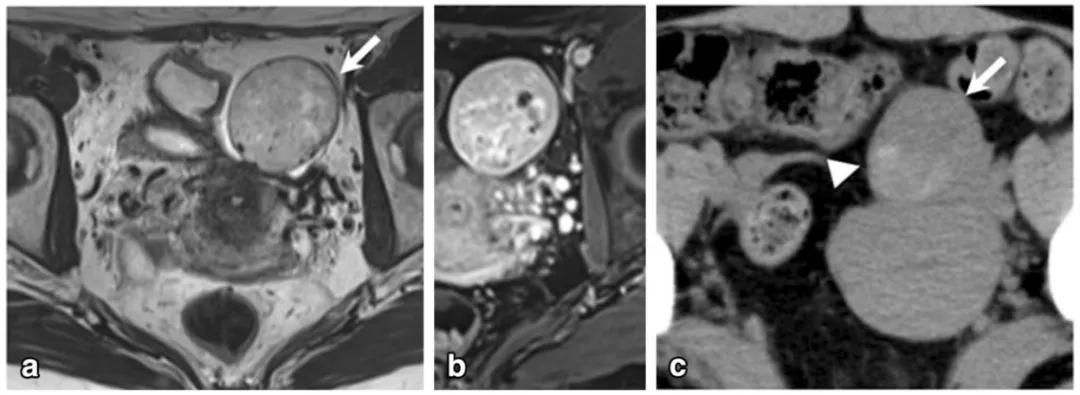

女,68 岁,左卵巢 Brenner 瘤。T2WI 显示左侧卵巢巨大低信号肿物(图 a),CT 扫描显示 8 年后肿物增大、多发钙化、发生囊变(图 b)。